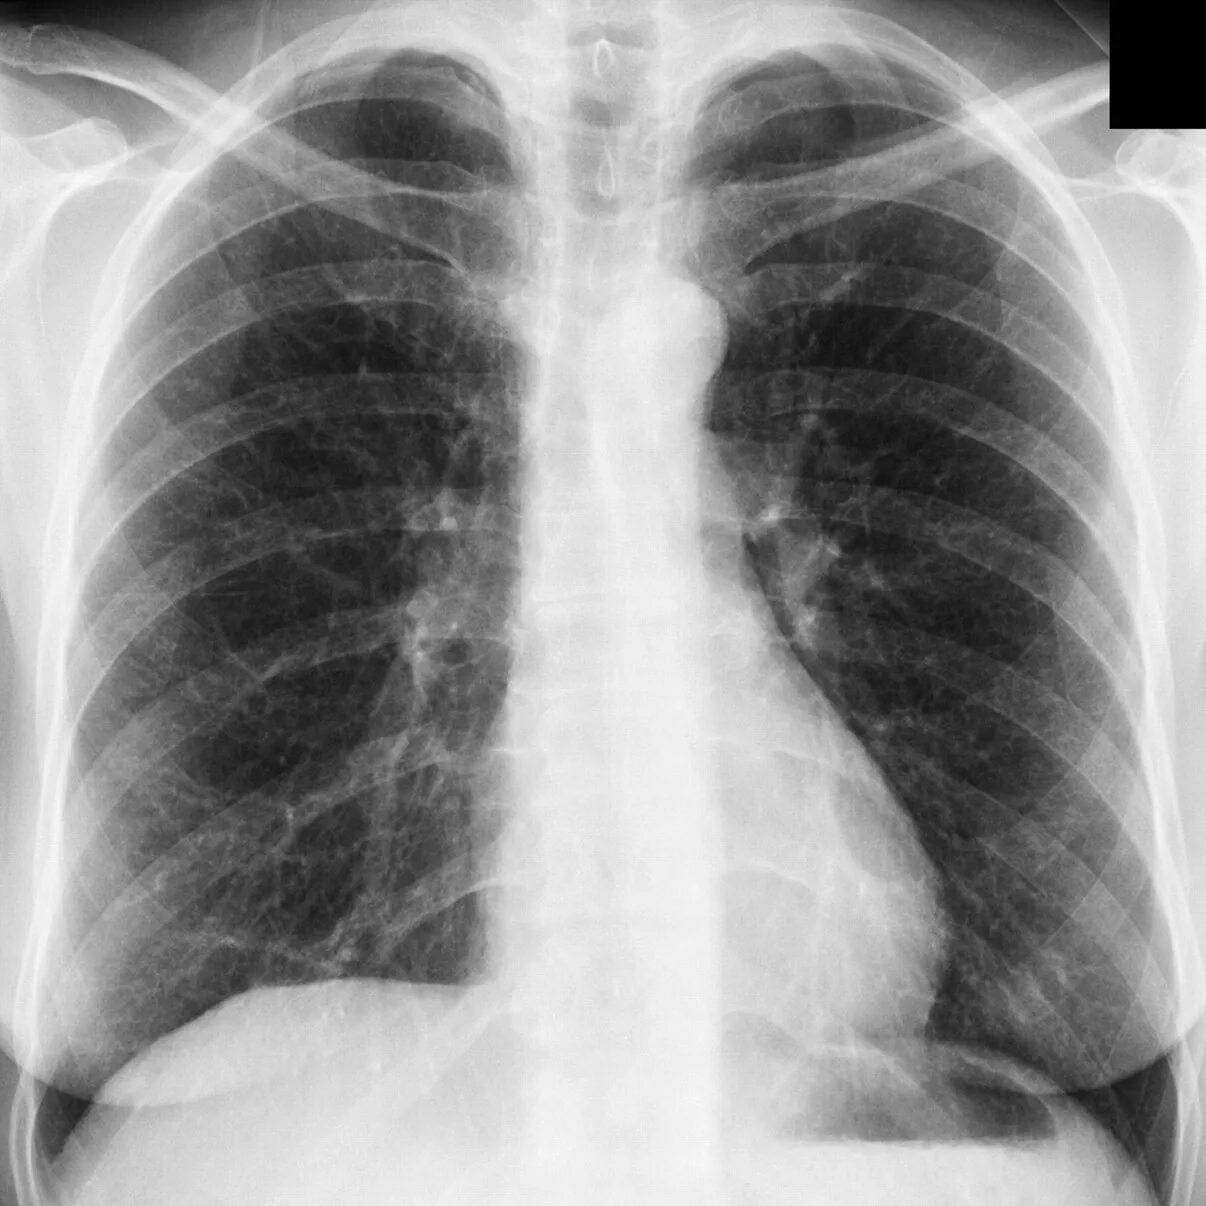

Пневмосклероз легких прогноз